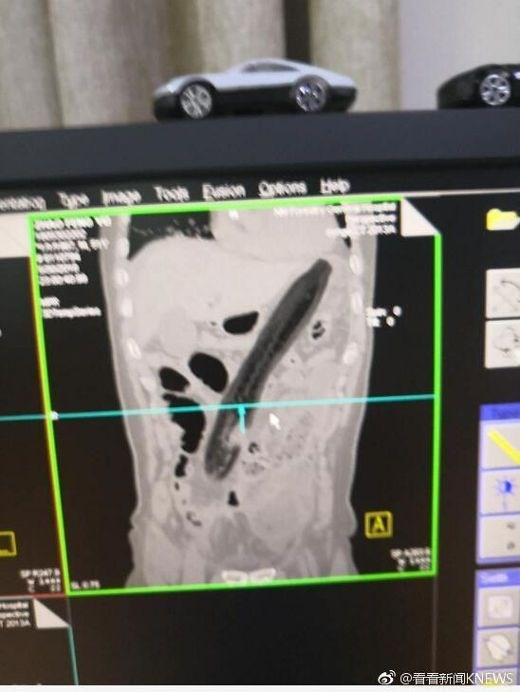

Old  Default Suýt chết vì nhét cà tím vào hậu môn để chữa táo bón?

Thật hết chịu nổi với người đàn ông này. Ông ta không biết nghe ai mà có thể chữa táo bón bằng cách nhét cả quả cà tím dài ngoằng vào hậu môn? Thật ai cũng chết khiếp với ông.

Sau khi bị đau bụng và táo bón trong 2 ngày, một người đàn ông Trung Quốc đã quyết định nhét một quả cà tím khổng lồ vào hậu môn.

Tuy nhiên, loại quả này không hề có tác dụng trong việc giải quyết vấn đề của người đàn ông 50 tuổi mà chỉ khiến ông ta cảm thấy đau và khó chịu hơn.

Thậm chí, ông ấy còn có cảm giác buồn nôn.Theo Shanghaiist, cuối cùng, không thể chịu đựng, ông ta đã đến bệnh viện.Kết quả chụp X-quang cho thấy quả cà tím quá lớn và bị đẩy lên tận phía trên làm tổn thương phổi của ông ấy.Bác sỹ đã rút "vật thể lạ" ra ngoài và đo được nó dài khoảng 30cm.